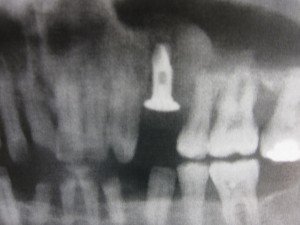

術後のパノラマレントゲンです。